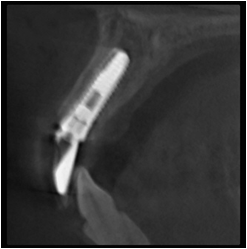

CT画像です。

インプラント埋入後のレントゲン写真